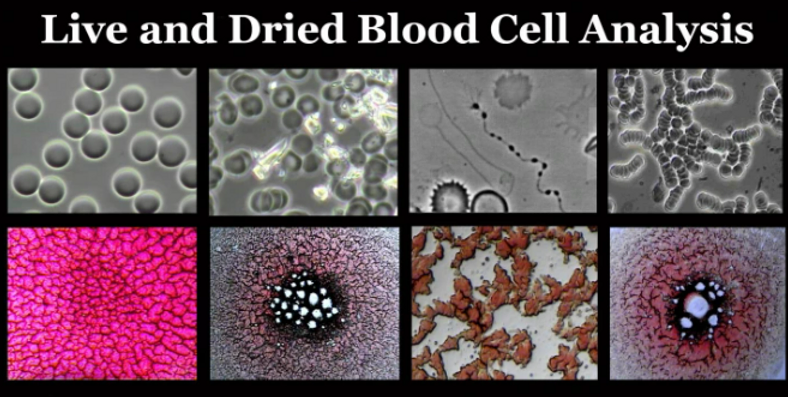

Micrographs of Healthy and UnHealthy Blood Under pHase Contrast and Brightfield Microscopy

In the Following Video Dr. Young Shares His Work, Research and Findings in a Demonstration of Live and Dried Blood Analysis Using Phase Contrast and Brightfield Microscopy: